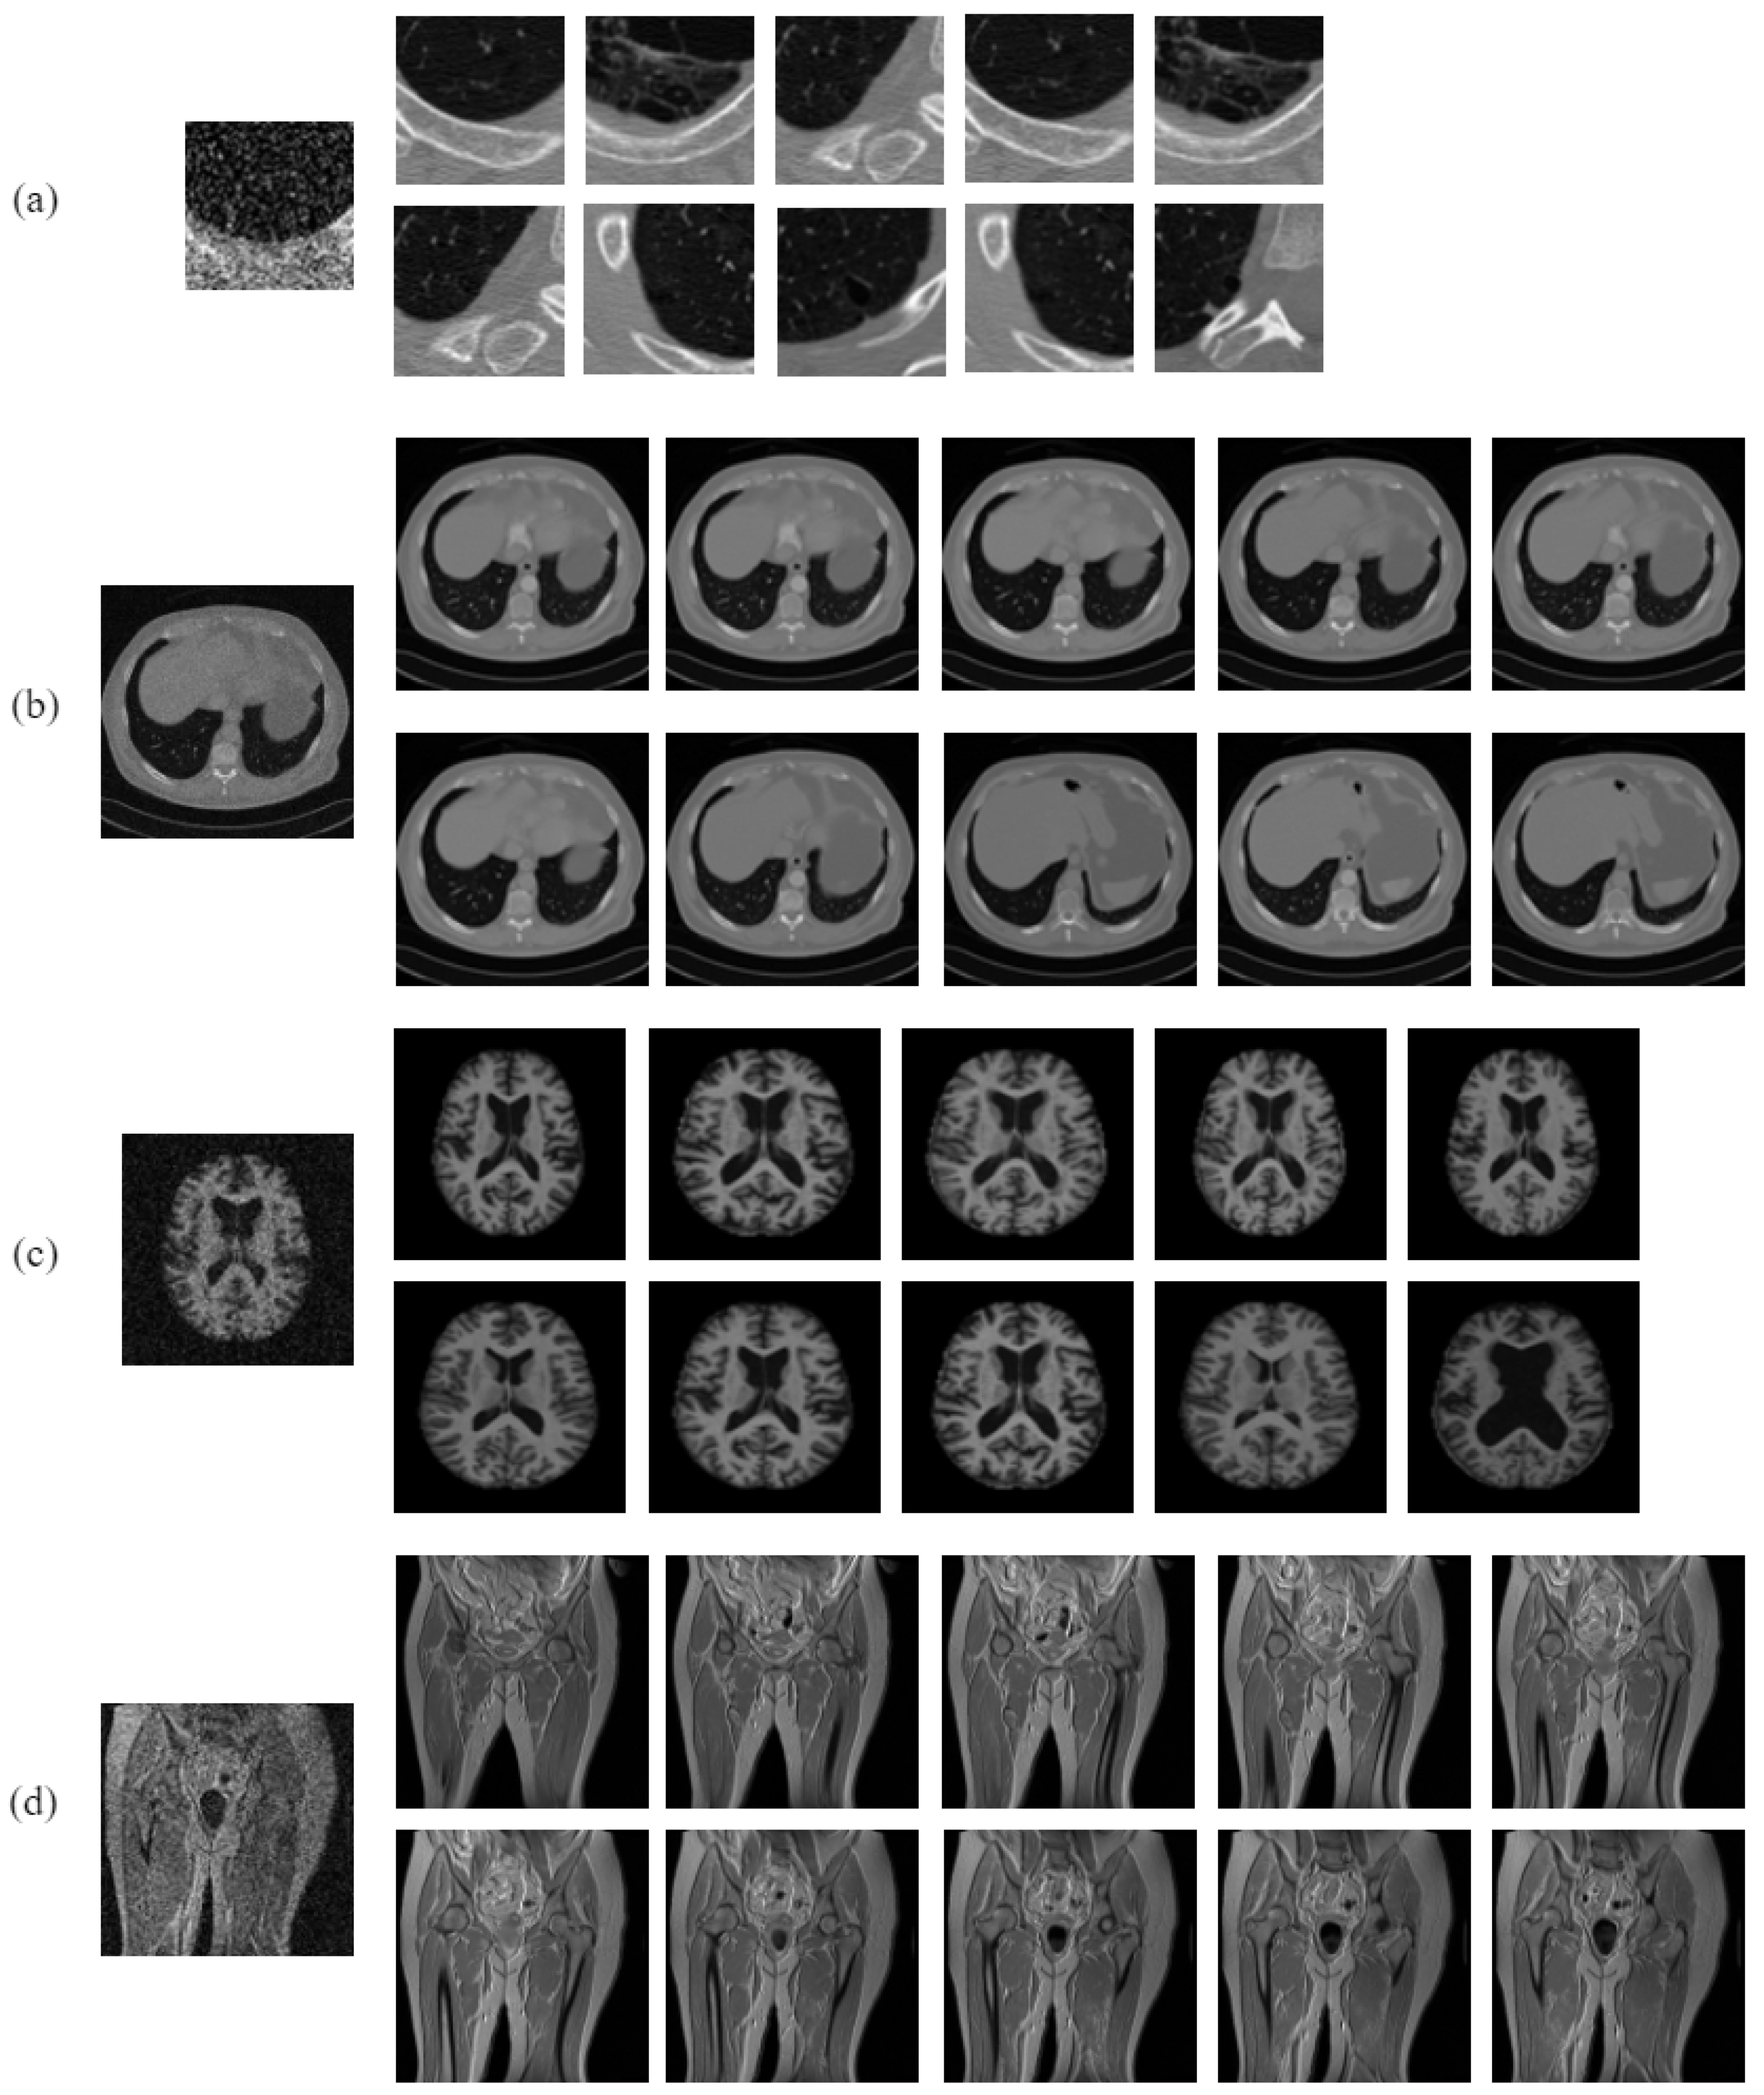

4.1. Performance Analysis on Noise-Free Images

3.3. Dataset Description